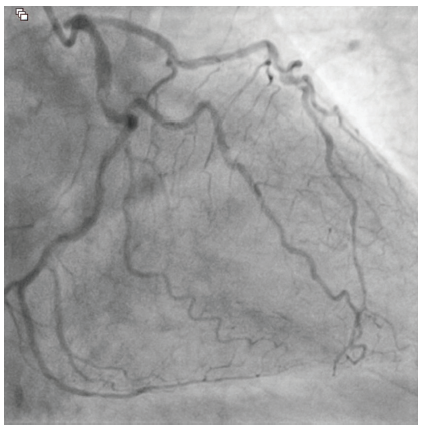

An 81-year-old male with hypertension, diabetes, and hyperlipidemia was referred for evaluation of an abnormal stress test. He originally complained of shortness of breath with exertion. A pharmacologic stress test was performed at an outside facility and showed inferior wall ischemia with a normal ejection fraction. He underwent coronary angiography via a right radial approach that revealed a heavily calcified, eccentric lesion in the large, codominant circumflex artery with TIMI-3 flow (Figure 1). Due to a small ulnar artery, the decision was made to access the right femoral artery in preparation for complex intervention. Utilizing a 6 French Judkins Left 4 guide catheter, the left system was engaged. The lesion was wired with a Runthrough® Izanai™ wire (Terumo Interventional Systems) and pretreated with balloon angioplasty using a 2.0 mm x 15 mm Takeru™ RX balloon (Terumo Interventional Systems) (Figure 2). A 2.5 mm x 15 mm Takeru™ RX noncompliant (NC) balloon was then advanced to perform further pre-dilation balloon angioplasty (Figure 3).